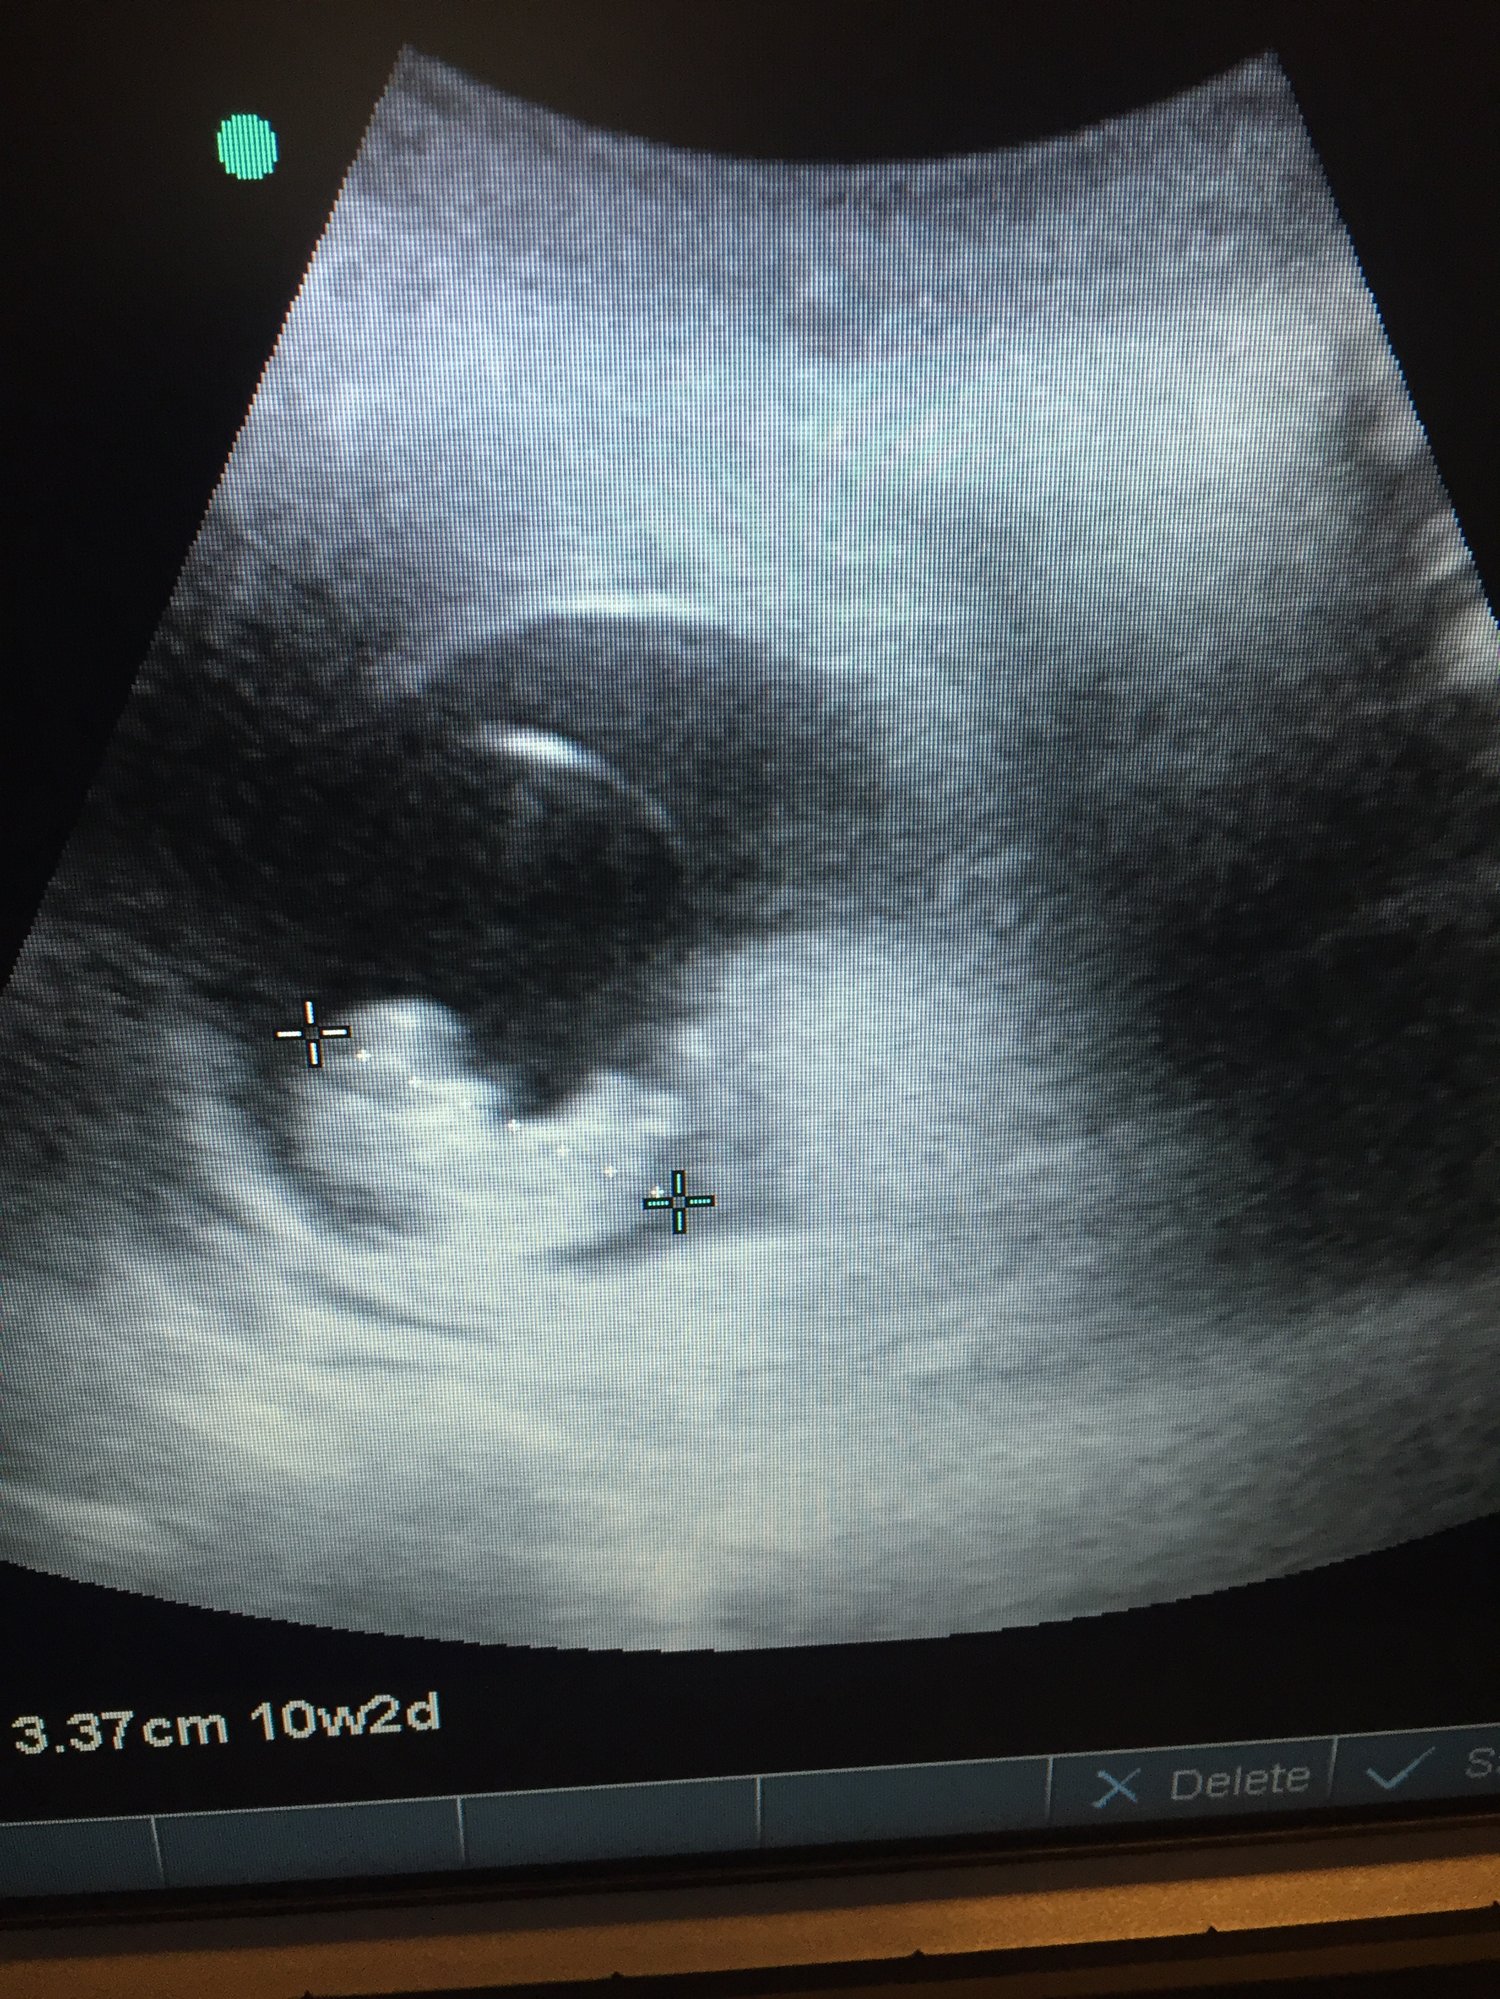

First appt with our midwife. 10w2d. Tracking exactly where we thought we were. When the image came up our three year old said, "it's a baby!"